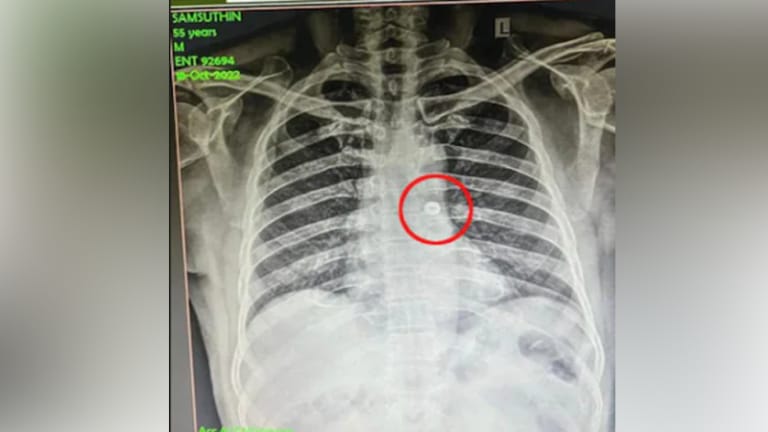

ಎಲೆಕ್ಟ್ರೀಷಿಯನೊಬ್ಬರು ಹೋಗಿ ಹೋಗಿ ನಟ್  ಒಂದನ್ನು ನುಂಗಿದ್ದು ವೈದ್ಯ ಲೋಕಕ್ಕೆ ಅಚ್ಚರಿ ಜತೆಗೆ ತಲೆಬಿಸಿ ಮೂಡಿಸಿದ್ದಾರೆ. ಇವರು ಯಾವುದೇ ಗಿನ್ನಿಸ್ ರೆಕಾರ್ಡ್ ಬರೆಯಲು ಹೋದವರಲ್ಲಾ, ಬದಲಿಗೆ ತಾನು ಕೆಲಸ ಮಾಡುತ್ತಿದ್ದ ಸಮಯದಲ್ಲಿ ನಟ್ ಅದು ಹೇಗೋ ಶ್ವಾಸಕೋಶಕ್ಕೆ ಪ್ರಯಾಣ ಬೆಳೆಸಿದೆ.

ಹಾಗೆ ನಟ್ ನುಂಗಿ ಪ್ರಾಣವನ್ನು ಇನ್ನೇನು ಕಳೆದು ಕೊಳುವ ಹಂತಕ್ಕೆ ತಲುಪಿದ ವ್ಯಕ್ತಿ ಕೊಯಮತ್ತೂರಿನ ಎಲೆಕ್ಟ್ರೀಷಿಯನ್ ಸಂಶುದ್ಧೀನ್ ಎಂಬಾತ.

ನಟ್ ದೇಹದ ಒಳಕ್ಕೆ ತಲುಪಿದ ತಕ್ಷಣವೆ ಆ ವ್ಯಕ್ತಿಯನ್ನು ಅಲ್ಲಿನ ಸ್ಥಳೀಯ ಸರ್ಕಾರಿ ಆಸ್ಪತ್ರೆಗೆ ದಾಖಲಿಸಲಾಗಿದೆ. ಅಲ್ಲಿನ

ಕಿವಿ, ಮೂಗು, ಗಂಟಲು ವಿಭಾಗದಲ್ಲಿ ಇವರನ್ನು ಪರೀಕ್ಷಿಸಿ ಎಕ್ಸ್-ರೆ ನಡೆಸಿದಾಗ ಈ ವೇಳೆಯಲ್ಲಿ ಶ್ವಾಸಕೋಶದಲ್ಲಿ ನಟ್ ಇರುವುದು ತಿಳಿದು ಬಂತು. ಅಲ್ಲದೆ ಆ ನಟ್ ಎಡ ಶ್ವಾಸಕೋಶದ ಕಡೆಗೆ ಹೋಗುತ್ತಿರುವುದು ವೈದ್ಯರಿಗೆ ತಿಳಿದು ಬಂದಿತ್ತು.

ತಕ್ಷಣವೇ ಚುರುಕುಗೊಂಡ ವೈದ್ಯರ ತಂಡವು ಎಲೆಕ್ಟ್ರೀಷಿಯನ್ ಸಂಶುದ್ಧೀನ್ ನನ್ನು ಎಂಡೋಟ್ರಾಶಿಯಲ್ ಉಪಕರಣವನ್ನು ಬಳಸಿ ಶಸ್ತ್ರಚಿಕಿತ್ಸೆ ಮಾಡಿದರು. ಕಿವಿ ,ಮೂಗು ಮತ್ತು ಗಂಟಲು ವಿಭಾಗದ ಮುಖ್ಯಸ್ಥ ಶರಣವನ್, ಅಲಿಸುಲ್ತಾನ್, ಮಣಿಮೋಳಿ ಸೆಲ್ವನ್ ಮತ್ತು ಮದನಗೋಪಾಲನ್ ಎಂಬ ವೈದ್ಯರ ತಂಡವು ಎಲೆಕ್ಟ್ರೀಷಿಯನ್ ನ ಪ್ರಾಣವನ್ನು ಉಳಿಸಿದ್ದಾರೆ.

ಎಲೆಕ್ಟ್ರೀಷಿಯನರಿಗೆ ಸಾಮಾನ್ಯವಾಗಿ ಒಂದು ಅಭ್ಯಾಸ ಇರುತ್ತೆ. ಬಾಯಲ್ಲಿ ಟೂಲ್ಸ್ ಹಿಡ್ಕೊಂಡು ಕೆಲಸ ಮಾಡುವುದು. ಈ ಎಲೆಕ್ಟ್ರೀಷಿಯನ್ ಕೆಲ್ಸ ಮಾಡುತ್ತಾ ಇರುವಾಗ, ಬಾಯಲ್ಲಿ ಬಹುಶಃ ನಟ್ ಒಂದನ್ನು ಹಿಡ್ಕೊಂಡ್ ಇದ್ದ ಅನ್ನಿಸುತ್ತೆ. ಅದು ಶ್ವಾಸಕೋಶದೊಳಗೆ ಹೋಗಿದೆ. ತಕ್ಷಣ ಕೆಮ್ಮಲು ಪ್ರಯತ್ನಿಸಿದ ಇವರಿಗೆ ನಟ್ ನಿಂದಾಗಿ ಉಸಿರುಗಟ್ಟಲು ಪ್ರಾರಂಭವಾಗಿದೆ. ತಕ್ಷಣ ವೈದ್ಯಕೀಯ ಸಹಾಯ ದೊರೆತ ಕಾರಣದಿಂದ ವ್ಯಕ್ತಿ ಬಚಾವಾಗಿದ್ದಾರೆ.